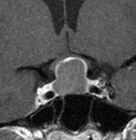

転移性脊髄腫瘍手術

後方からのアプローチにて脊髄の徐圧および腫瘍摘出を施行。多椎間にわたり後方固定および椎体切除を併せて施行した症例である。切除腔にケージを留置し椎体形成も行う。